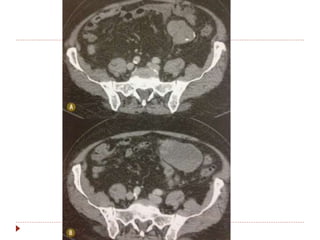

Outros critérios modificadores do RECIST

 Alguns tumores especiais já consideram densidade e

 GIST

 Boa resposta = redução de 10% dimensões e 15% da atenuação

na TC.

 Progressão = lesões novas, aumento tamanho 20% ou não

mudança de densidade.

Outros critérios modificadoresdo RECIST  Alguns tumores especiais já consideram densidade e padrão de realce.  Mesoteliomas  Medida dificultada pela curvatura da parede torácica.  Medir perpendicular a parede, em 2 locais, cada um em 3 níveis = soma das 6 medidas. Preferir porção superior do tõrax.  GIST  Boa resposta = redução de 10% dimensões e 15% da atenuação na TC.  Progressão = lesões novas, aumento tamanho 20% ou não mudança de densidade.  Hepatocarcinomas  Se tratados com embolização, radiofrequencia ou crioablação resposta se não houver realce periférico pelo contraste na TC ou RM.